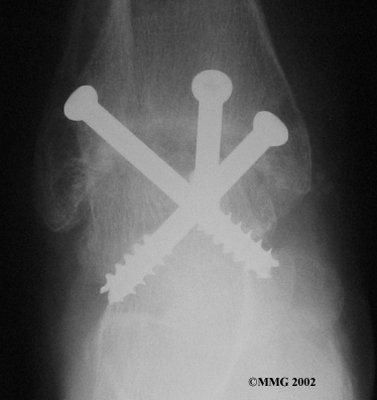

It is important when the surfaces are removed that the angles of the cut surfaces are correct. When the tibia is brought against the talus, the foot should be at a right angle to the lower leg. Once the cuts are made the bones must be held in place while they fuse. This can be done using large metal screws and metal plates if necessary. The screws are usually under the skin and are not removed unless they begin to rub and cause pain.

Inserting the screws